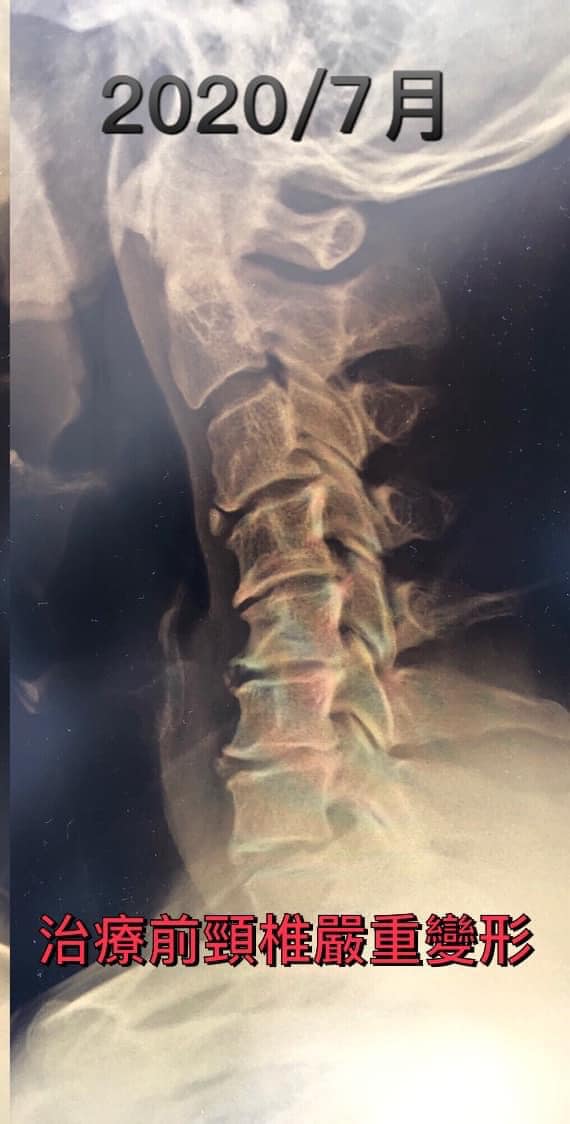

Cervical Spine Treatment Cases 頸椎治療案例 頸椎壓迫竟導致自律神經失調?耳鳴、心悸、暴瘦全因筋膜失衡! 2021.02.18 頸椎壓迫神經根導致工作受限?非手術微創療法改善關鍵公開 2021.02.17 頸椎脊髓壓迫五大症狀公開!你也有雙腳沉重、手腳麻電感嗎? 2021.01.15 長期頭痛吃藥沒效?小心你可能是「頸源性頭痛」患者 2021.01.07 #感謝新北市蘆洲區楊先生熱情見證 #頸椎病變引起肩膀痠痛無法睡眠 #曾經大痛到想立刻... 2020.12.31 #感謝新北三重劉小姐熱情見證 #神經根型頸椎病經典案例 #曾經手麻痛到無法騎摩托車 #... 2020.12.25 #遠從台東縣的熱情見證 #五個多小時的車程三百多公里很辛苦 #疼痛超過兩年打過頸椎三... 2020.12.24 #頸椎酸痛到無法睡覺是怎們回事 #醫學中心證實頸椎間盤突出 #神外醫師建議開刀但患者... 2020.12.19 #頸椎曲線弧度非常重要 #頸椎嚴重壓迫有可能逆轉嗎 #肩膀疼痛到不行合併走路都無力 #... 2020.12.09 頸椎退化壓迫神經根怎麼辦?大直林小姐四週見效的中醫微創療法 2020.12.08 #特殊案例長年過敏性鼻炎 #起因居然是頸椎交感神經筋膜壓迫 #打開椎動脈循環🔄找到解... 2020.12.05 #恭喜新店陳小姐頸椎療程畢業 #神經根型卡壓醫案 #頸椎整合中醫微創療法逆轉勝 #告別... 2020.11.24 #特殊案例頸椎手術後又再度突出案例 #感謝台中劉大哥熱情見證 #親自手捏醫師娃娃公仔... 2020.11.18 #頸椎病居然會導致手快速萎縮 #脊髓型頸椎病案例 #感謝高雄王大哥熱情見證 #頸椎整合... 2020.11.13 #神經根型頸椎病讓人痛到無法入眠 #感謝新店陳小姐熱情見證 #患者的疼痛日誌讓人感動 ... 2020.11.11 ← 上一頁 3 4 5 6 7 下一頁 →